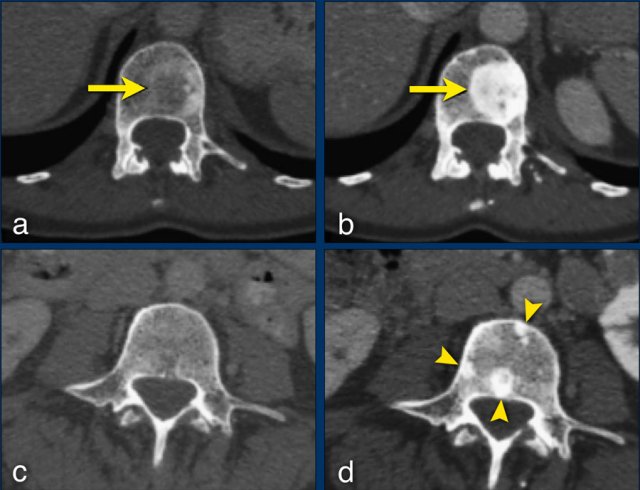

CT-images in a 81-year-old female with endometrial carcinoma and occurrence of new liver metastases during treatment with chemotherapy.

Any new lesion means progressive disease, but not every newly detected lesion is always a true new lesion.

In osteolytic bone metastases it can be difficult to determine if a sclerotic lesion that is detected during follow up is truly a new lesion.

The sclerotic bone lesions in b and d are not new metastases but an osteoblastic reaction to the therapy.